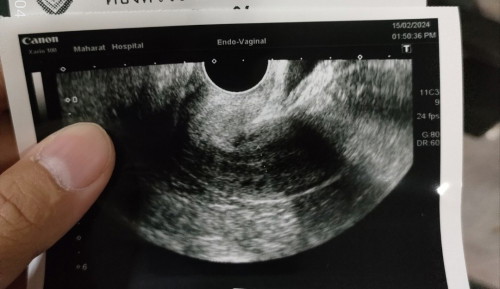

แม่ๆคนไหนประจำเดือนขาดแช้วไปซาวด์ท้องเลยไหมค่ะ พอดีประจำเดือนขาดมา2เดือนแล้ว พอไปซาวด์ก็เจอตามลักษณะในภาพเลยค่ะ#ขอบคุณล่วงหน้าสำหรับความคิดเห็นค่ะ #แนะนำกันหน่อยนะค่ะ

ประจำเดือนขาด 3วัน ตรวจขึ้น2ขีดเข้มมาก ไปหาหมอหมอให้ตรวจฉี่และตรวจเลือดซ้ำเพื่อหาค่าการตั้งครรภ์ ผลเลือดออกมาว่าท้องจริงๆ หมอถึงส่งซาวมดลูกค่ะ ซาวแล้วไม่เจอถุงไม่เจอไข่แดง เนื่องจากไม่เจอถุงการตั้งครรภ์ หมอกังวลว่าจะท้องนอกมดลูก เลยได้นอนแอดมินรพ.ต่ออีก3วัน เพื่อเช็คเลือดว่าค่าการตั้งครรภ์เพิ่มขึ้นไหมทุกๆวัน และซาวมดลูกดูถุงการตั้งครรภ์ เท่ากับว่า6วันเจอถุงการตั้งครรภ์แล้วค่ะ แต่ยังไม่เจอไข่แดง หมอนัดอีก2อาทิตย์มาซาวมดลูกใหม่ รอบนี้เจอถุงการตั้งครรภ์ เจอไข่แดง แต่ตัวไม่ชัดเจนฟันธงไม่ได้ นัดมาอีก4วันรอบนี้เจอทุกอย่างค่ะพร้อมได้ฟังเสียงหัวใจ สรุปสั้นๆ1เดือนก็เห็นเกือบหมดแล้วค่ะถ้าท้องจริง หลักๆคือต้องเห็นถุงการตั้งครรภ์และไข่แดงใน1เดือน เป็นไปไม่ได้ที่2เดือนไม่มีแต่แต่ถุงการตั้งครรภ์ ไม่มีถุงการตั้งครรภ์=ไม่ท้องค่ะ

อ่านเพิ่มเติมปจด.ขาด2เดือนถ้าท้องจริงๆ รูปจะต้องไม่ใช่แบบนี้ค่ะ

ไม่รู้ว่าท้องหรือไม่ท้องค่ะ ช่วยดูให้หน่อยค่ะ